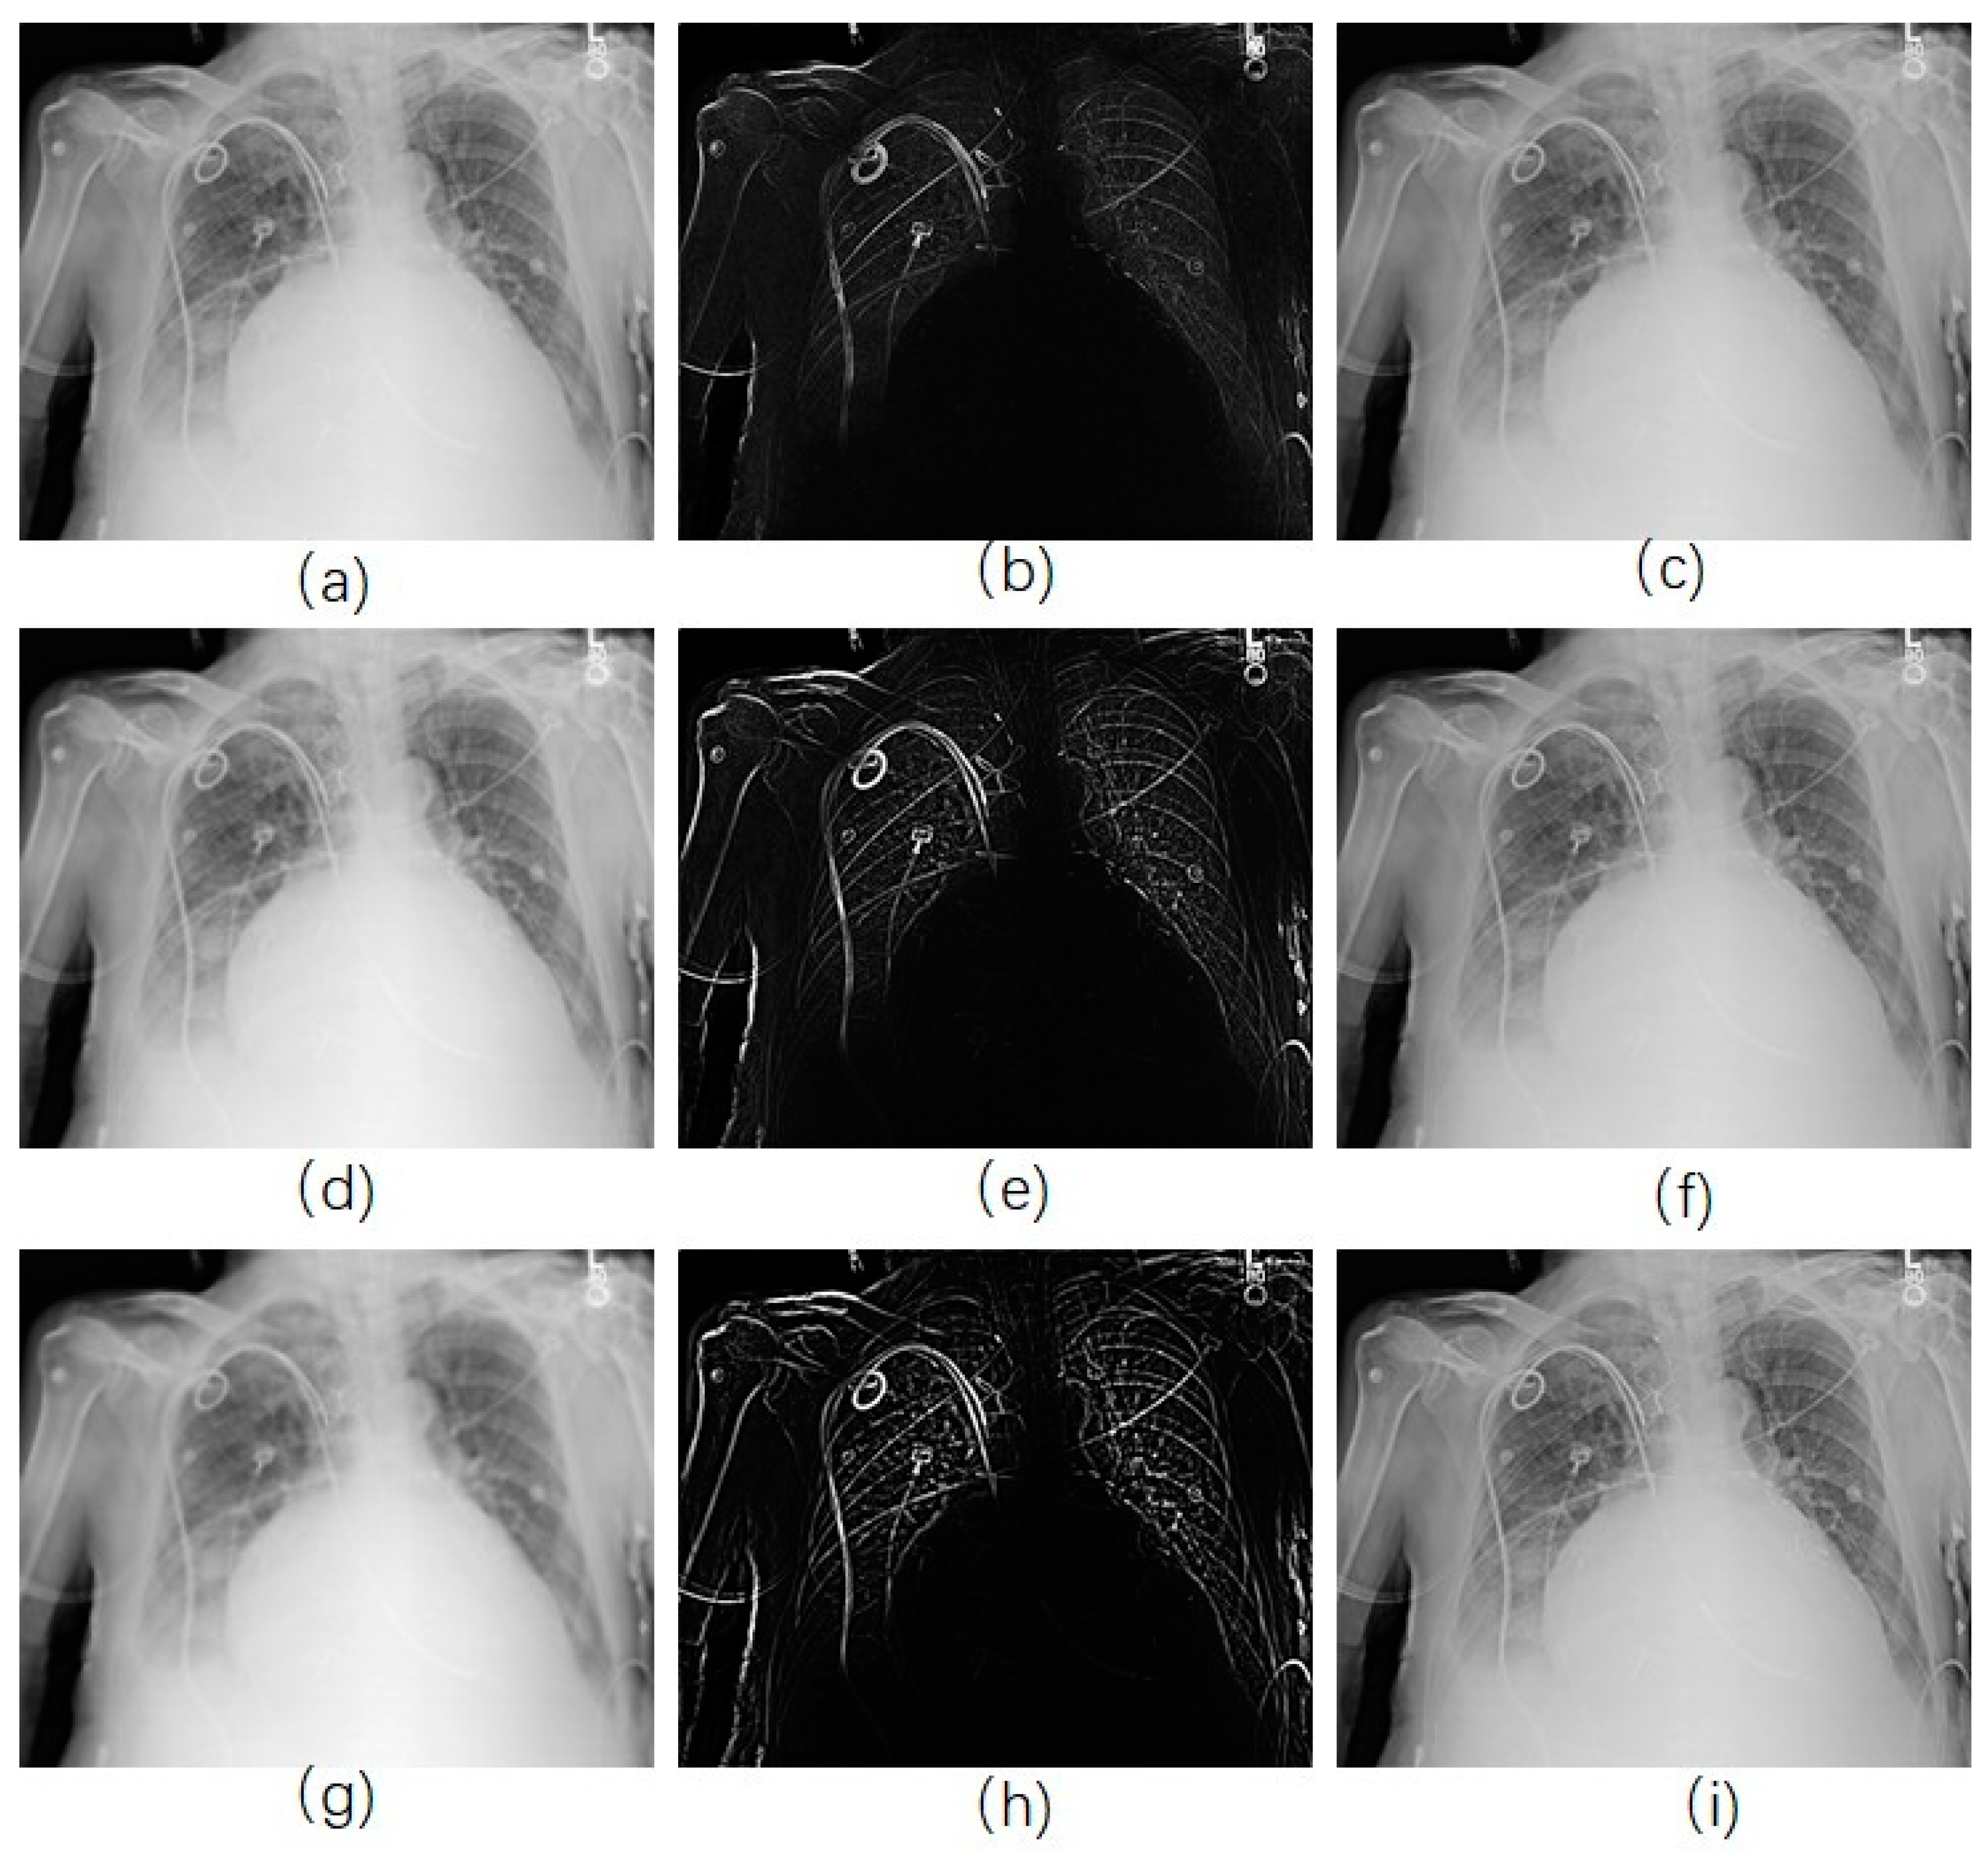

Once the edge-smoothed image is acquired by using RAD algorithm (Figure 2h), we subtract it from the original image to get the unsharp mask (Figure 2i), and then it is added to the original image (Figure 2j). Figure 2h shows that the edges in the image were smoothed and the noise was kept when the RAD algorithm was used, while the noise in Figure 2b were smoothed as well as the edges. In the final enhanced image, only the edges were enhanced in Figure 2j, while noise in Figure 2d, where the Gaussian smoothing method was used, was more obvious than that in the original image. Figure 2e shows the smoothed image acquired by using classical anisotropic diffusion. Only noise was enhanced in Figure 2g.

Figure 2.

Image enhancement by use of different model. (a) Original image; (b) image smoothed by Gaussian kernel; (c) unsharp mask by subtracting (b) from (a); (d) enhanced image by adding (c) with (a); (e) smoothed image by use of traditional anisotropic diffusion; (f) Unsharp mask; (g) enhanced image; (h) smoothed image by use of reversed anisotropic diffusion; (i) Unsharp mask; (j) enhanced image.